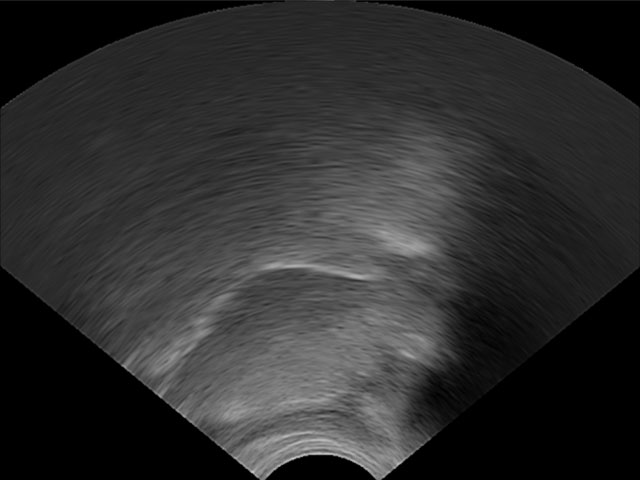

LinguaSound 3D, which is language independent, can simplify the interpretation of conventional ultrasound tongue imaging. A comparison of both imaging techniques is illustrated below for a normal English speaker:

| Conventional ultrasound tongue imaging | LinguaSound 3D | |

|---|---|---|

| Retroflex /r/ | ![]() |

![]() |